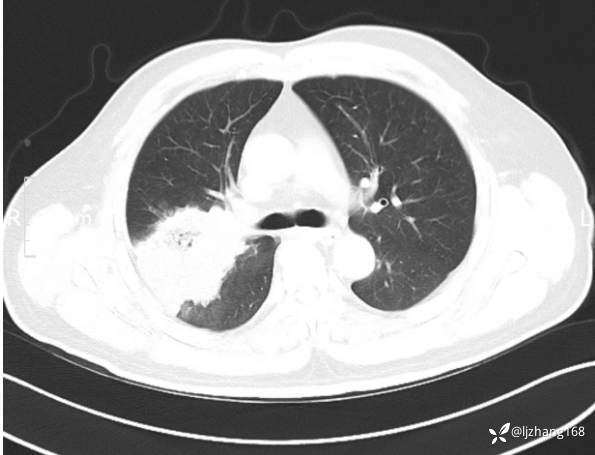

中年男患,右肺团片影,炎症0R肿瘤?

辅助检查:糖化血红蛋白12.3%。肺炎支原体IgG、IgM、呼吸道合胞病毒均未见明显异常。胸部CT:右肺上叶阻塞性肺炎。